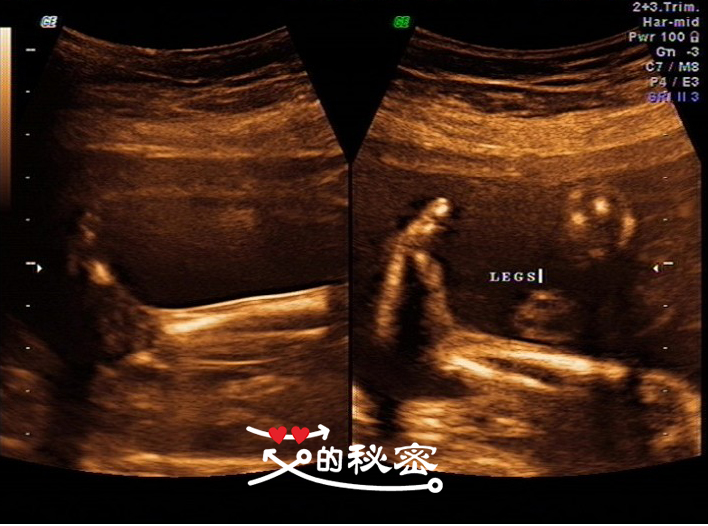

11、胎儿四肢:双侧肱骨、尺桡骨、股骨、胫腓骨可显示,双足可见,双手可见,四肢指(趾)分辨困难,英文FEET双脚,LEGS双腿,ARMS双臂,HAND双手。

5、其它畸形:排查腹部畸形、肢体畸形,先天性心脏病及畸胎病等,通过逐一观察排除胎儿畸形。如图:腿、脚、臂、骨长、心脏等。